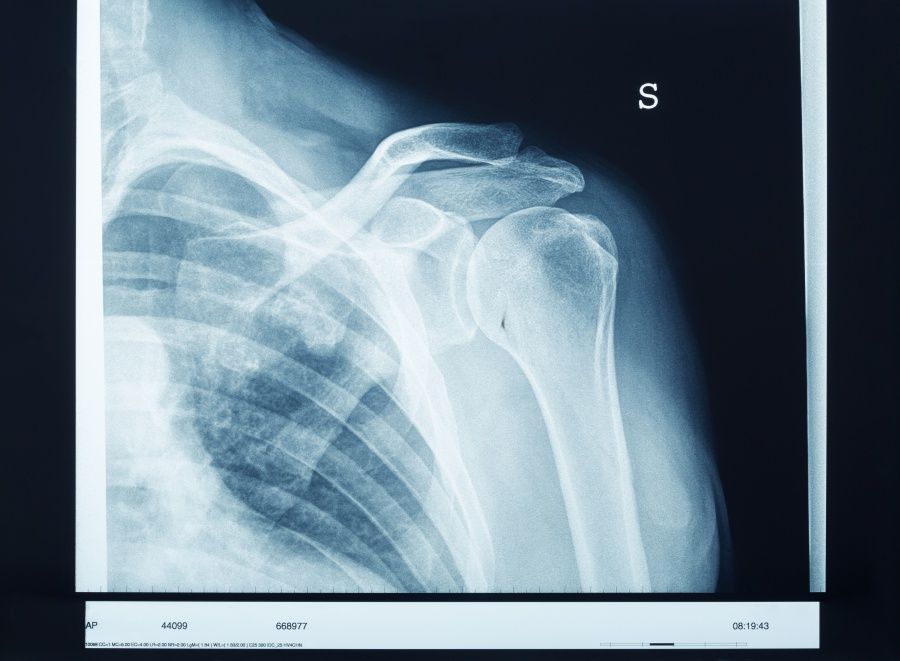

Das Schultergelenk ist das dritthäufigste Gelenk, an dem eine generalisierte Verschleißerkrankung vorkommt. Eine derartige Erkrankung in Form von Arthrose am Schultergelenk nennt man Omarthrose. Welche konservativen Therapien helfen? Wann ist eine OP notwendig?

Das Oberarmkopf-Pfannen-Gelenk wird durch die Rotatorenmanschette in Position gehalten und zentriert. Kommt es im Rahmen der Verschleißerkrankung zu einem oder mehreren Sehnenrissen, steigt der Oberarmkopf unter dem Schulterdach nach oben. Im Rahmen der generellen Verschleißerkrankung werden oft Knorpel verbraucht, die knöchernen Gelenkpartner deformiert und der Kapsel-Band-Apparat durch die Knorpelabriebpartikel chronisch entzündet.

Mit zunehmendem Verschleißgrad reichen diese ‘Hausmittel’ nicht mehr aus. Jetzt sollte ein Facharzt für Orthopädie und Unfallchirurgie aufgesucht werden. Er untersucht Sie und macht Röntgenaufnahmen, um den Verschleißgrad des Gelenkes zu bestimmen. Ergänzend wird eine Ultraschalluntersuchung durchgeführt, um festzustellen, ob ein Sehnenriss vorliegt.